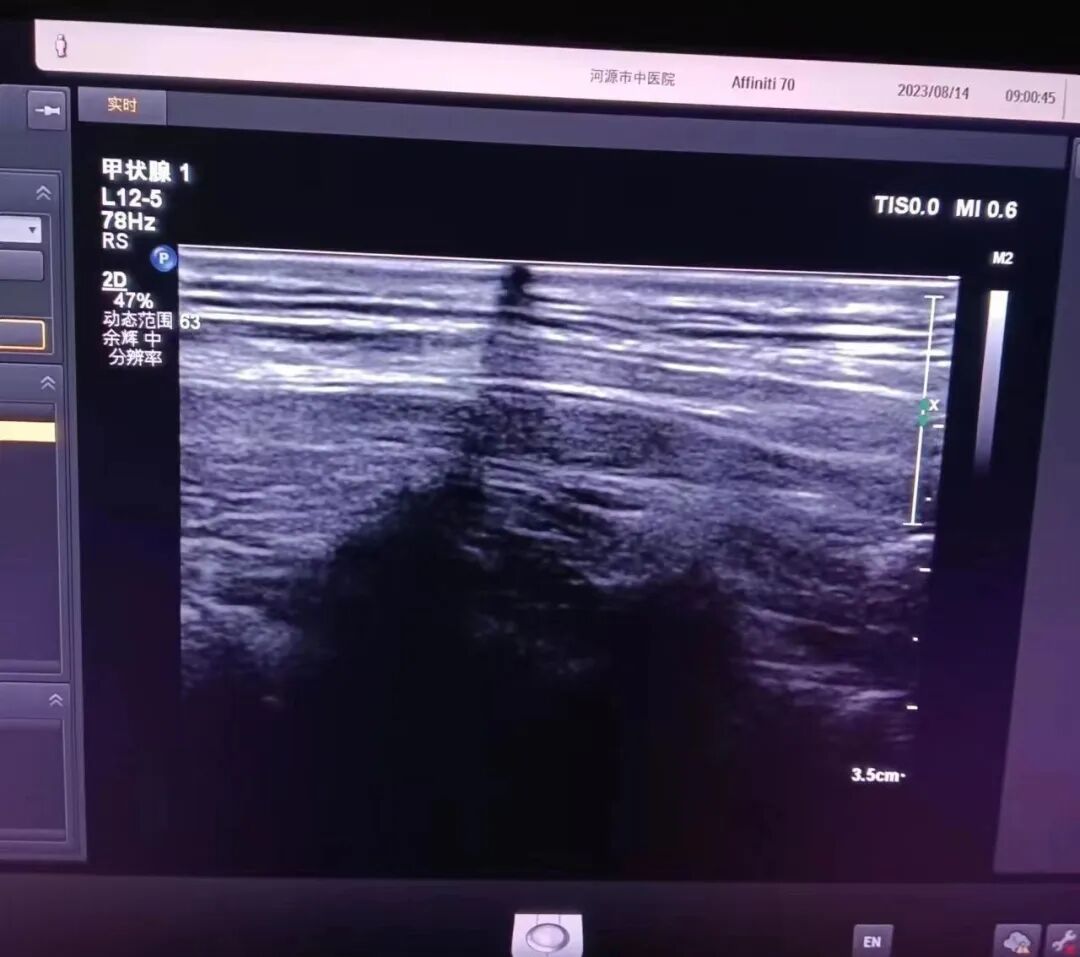

1. 故障现象

图像有暗道,具体如图所示:

2.故障检测

(2)上机检测,图像有暗道。

3.故障判定与分析

长期使用导致声头衰减,显示图像异常,声头晶体坏。